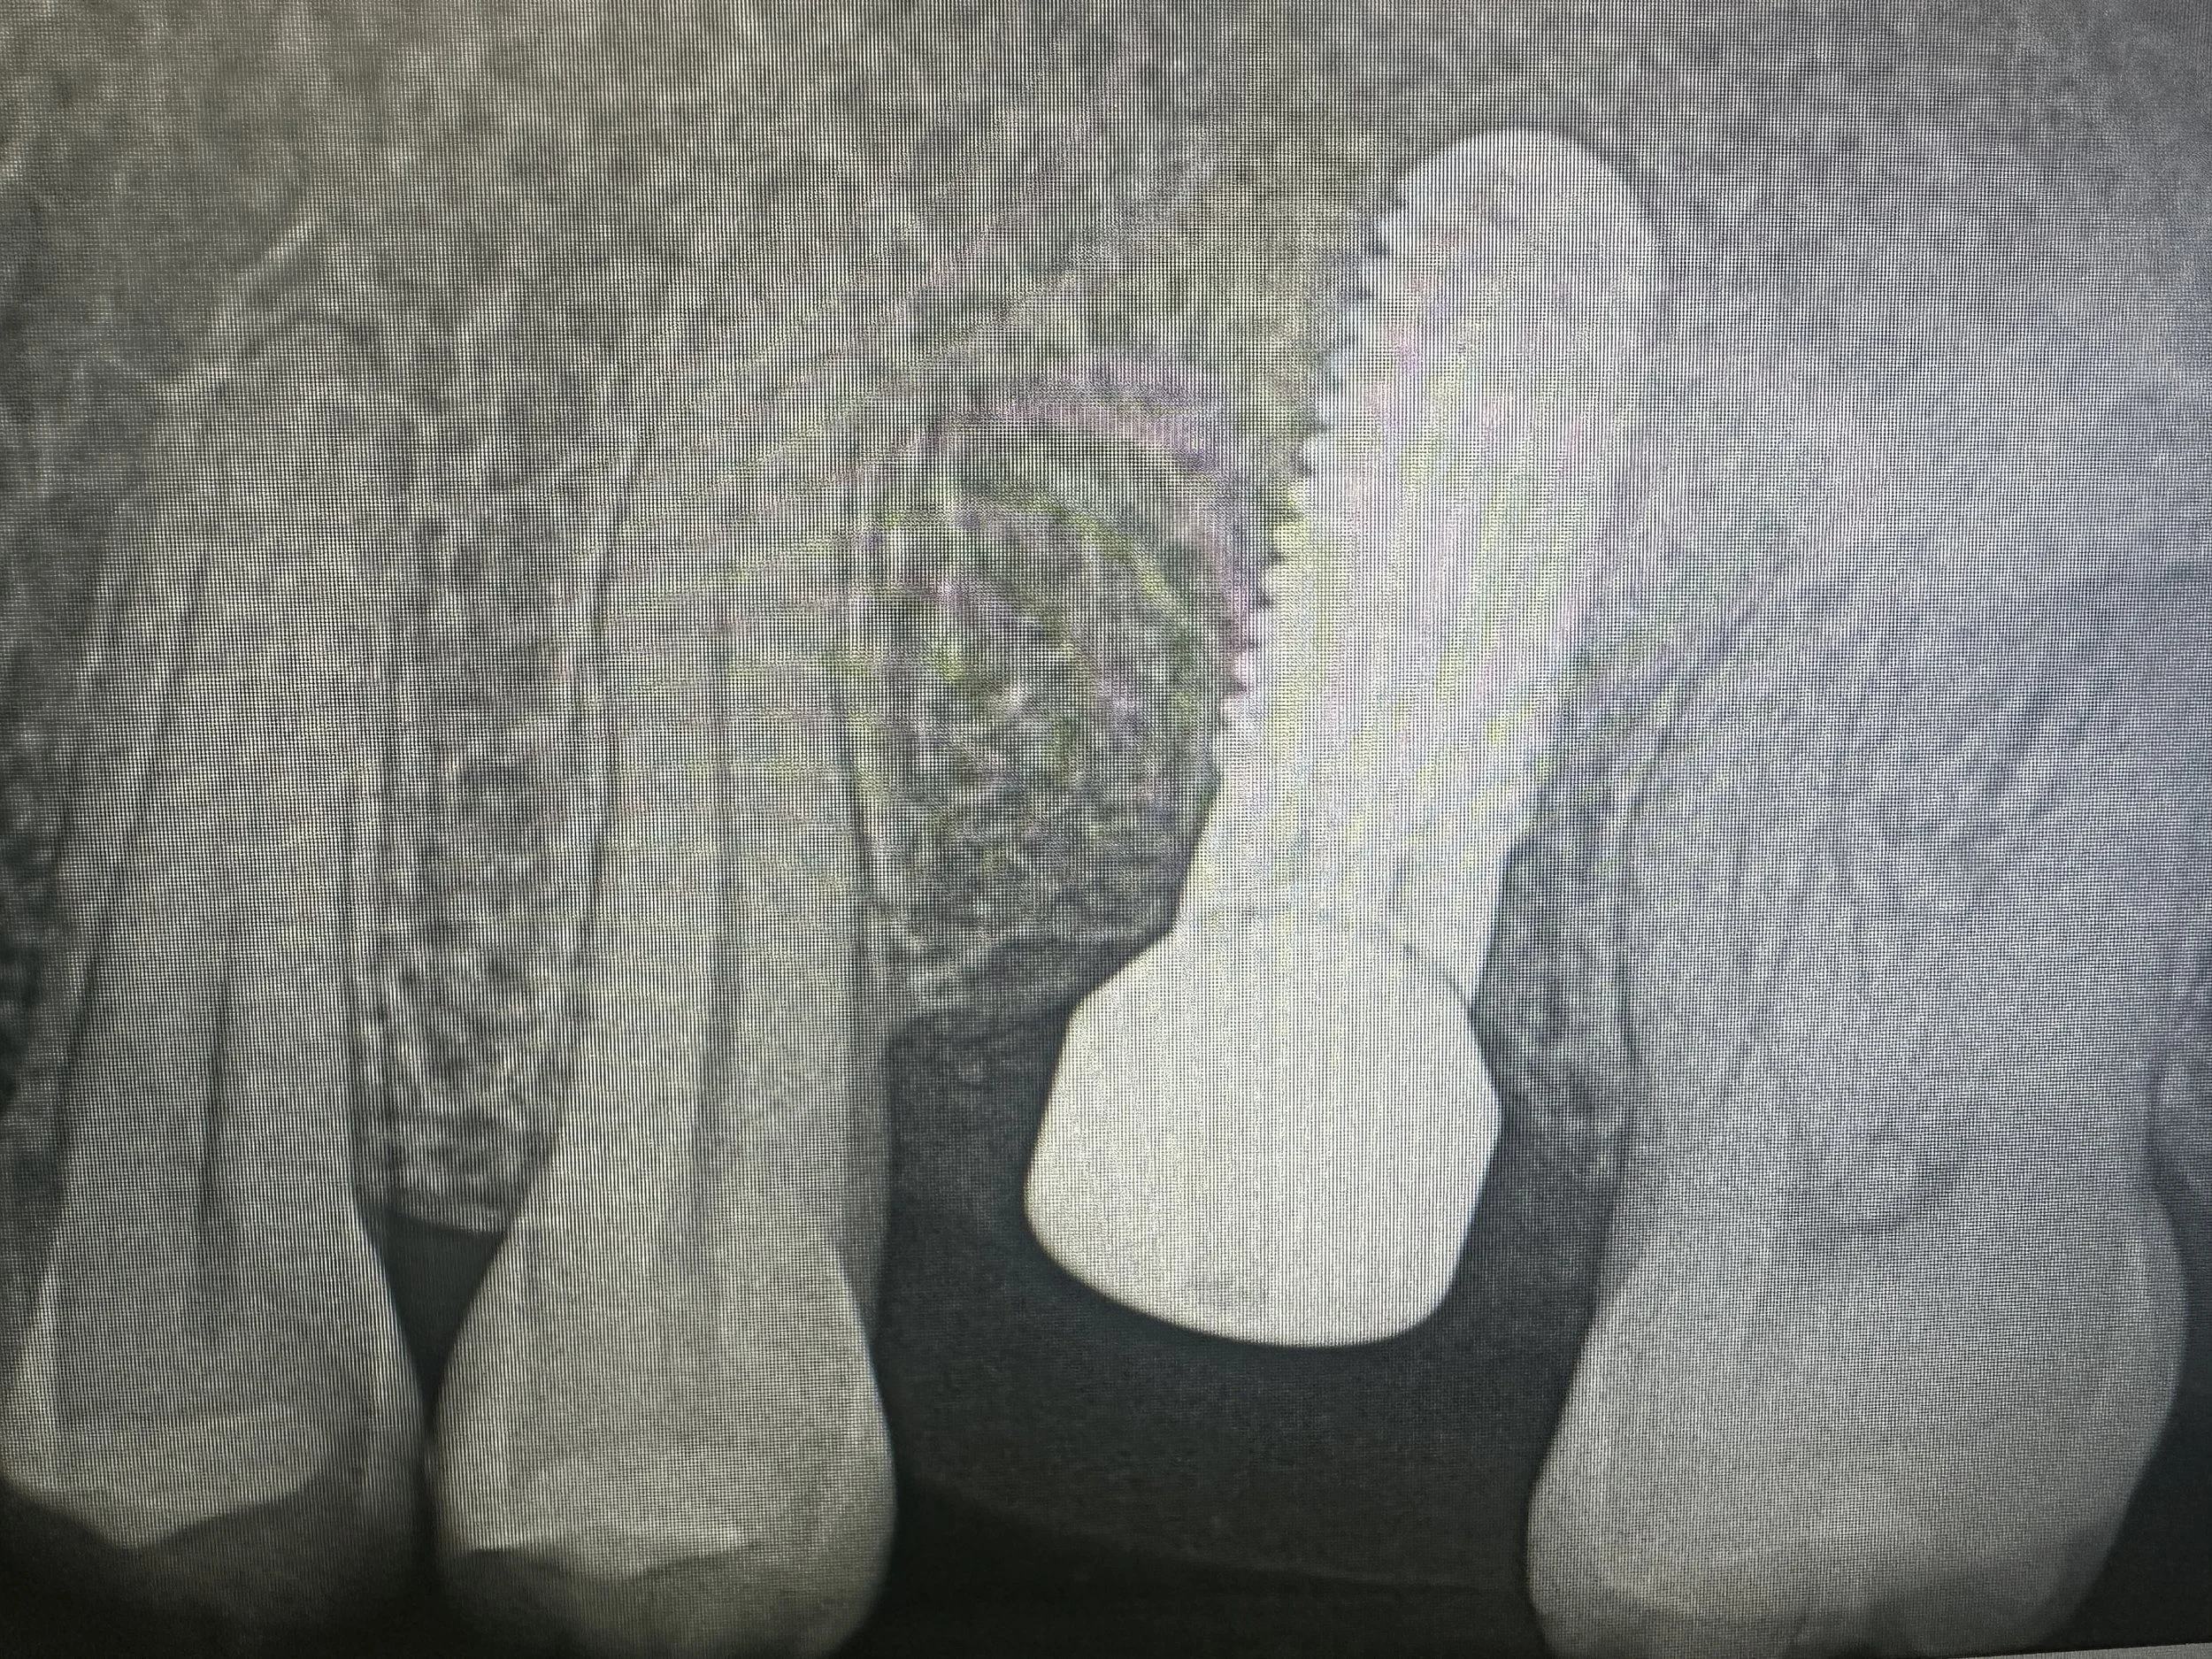

To restore the foundation for implant placement, a left maxillary lateral window sinus lift was performed. This technique allowed for controlled elevation of the sinus membrane and precise placement of bone graft material, increasing available bone volume while preserving surrounding anatomy.

Following adequate healing and bone maturation, implant placement at site #14 was completed with improved structural support and optimal positioning. Post-operative imaging demonstrated successful bone regeneration and stable integration of the implant within the augmented site.